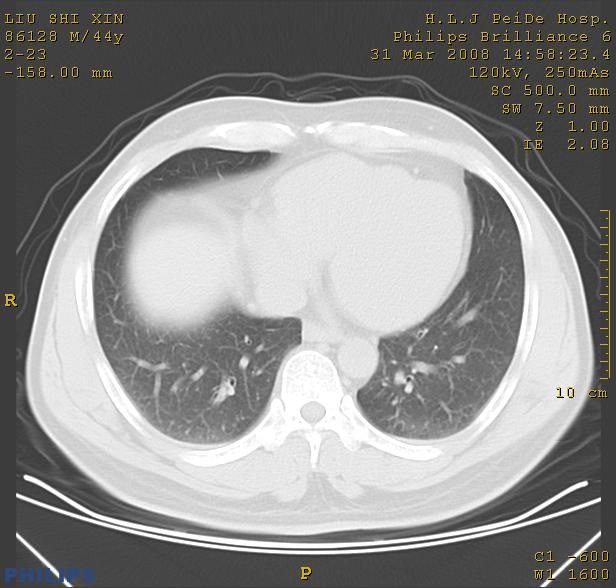

标题: CT13096:请分析胸膜下结节的影像基础是什么 有病理结果 [打印本页]

标题: CT13096:请分析胸膜下结节的影像基础是什么 有病理结果

瘢痕挛缩,胸膜牵拉,血管纠集扭曲,上叶前段支气管显示欠清,周围散在斑片影,以纵隔旁肺癌可能性大。请穿刺检查。

中心型肺癌并阻塞性肺炎、两肺及胸膜多发转移。

结节灶与血管末梢相通象转移灶;小三角状尖部有纤维索是胸膜拉扯征;纵隔旁大片实性影有点状钙化;周围有名显纤维瘢痕征可考虑瘢痕癌

本病例有病理结果是,鳞状上皮癌,胸膜下结节影病现诊断的肿大淋巴结,谢谢大家分析,请问胸膜下结节是肿大淋巴结怎么解释